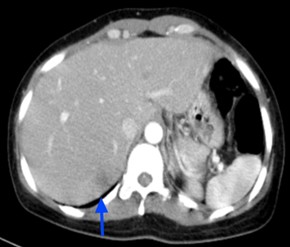

Làm các xét nghiệm khác tầm soát toàn thân phát hiện thêm các tổn thương tại gan và xương cánh chậu 2 bên.

Hình 5: Tổn thương gan trước điều trị: khối giảm tỷ trọng ở hạ phân thùy S7, kích thước 37x45mm, ngấm thuốc kém sau tiêm.

Hình 12: Hình  ảnh CT ổ bụng sau 6 tháng điều trị: Khối nhu mô gan hạ phân thùy S7 giảm tỷ trọng, ngấm thuốc kém sau tiêm,

Kích thước tổn thương giảm dần qua  các đợt   điều  trị: và 15mm (mũi tên xanh).